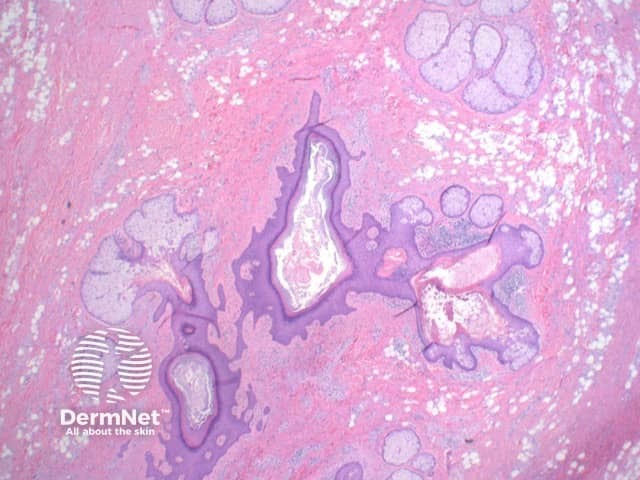

Scanning view shows dilated follicular structure or structures, with radiating mature sebaceous lobules (figures 1, 2). Surrounding the distorted hair follicles there may be thin anastomosing epithelial strands (figure 3). The stroma surrounding the epithelial units is frequently composed of dense collagenous tissue (figure 1-3) and can show prominent clefting to the surrounding adjacent uninvolved dermis (figure 1). Additional stromal changes can include increased vascularity or pockets of adipocytes consistent with increased stromal fat (figure 4).

Figure 2